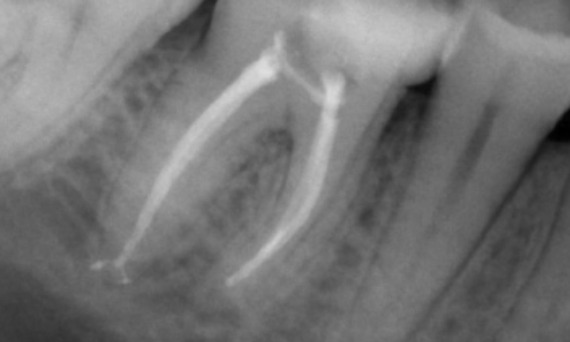

Antes: Radioluscência periapical associada principalmente à raiz distal e perda da lâmina dura na raiz mesial.

Depois: TruNatomy foi escolhido neste caso para permitir uma abordagem alavancada da cárie dental e um foco na preservação da dentina pericervical, especialmente no aspecto mesial, onde o dente teve uma restauração mais mínima.

Dr. Jonathan Cowie (especialista em endodontia)

Bath, Reino Unido